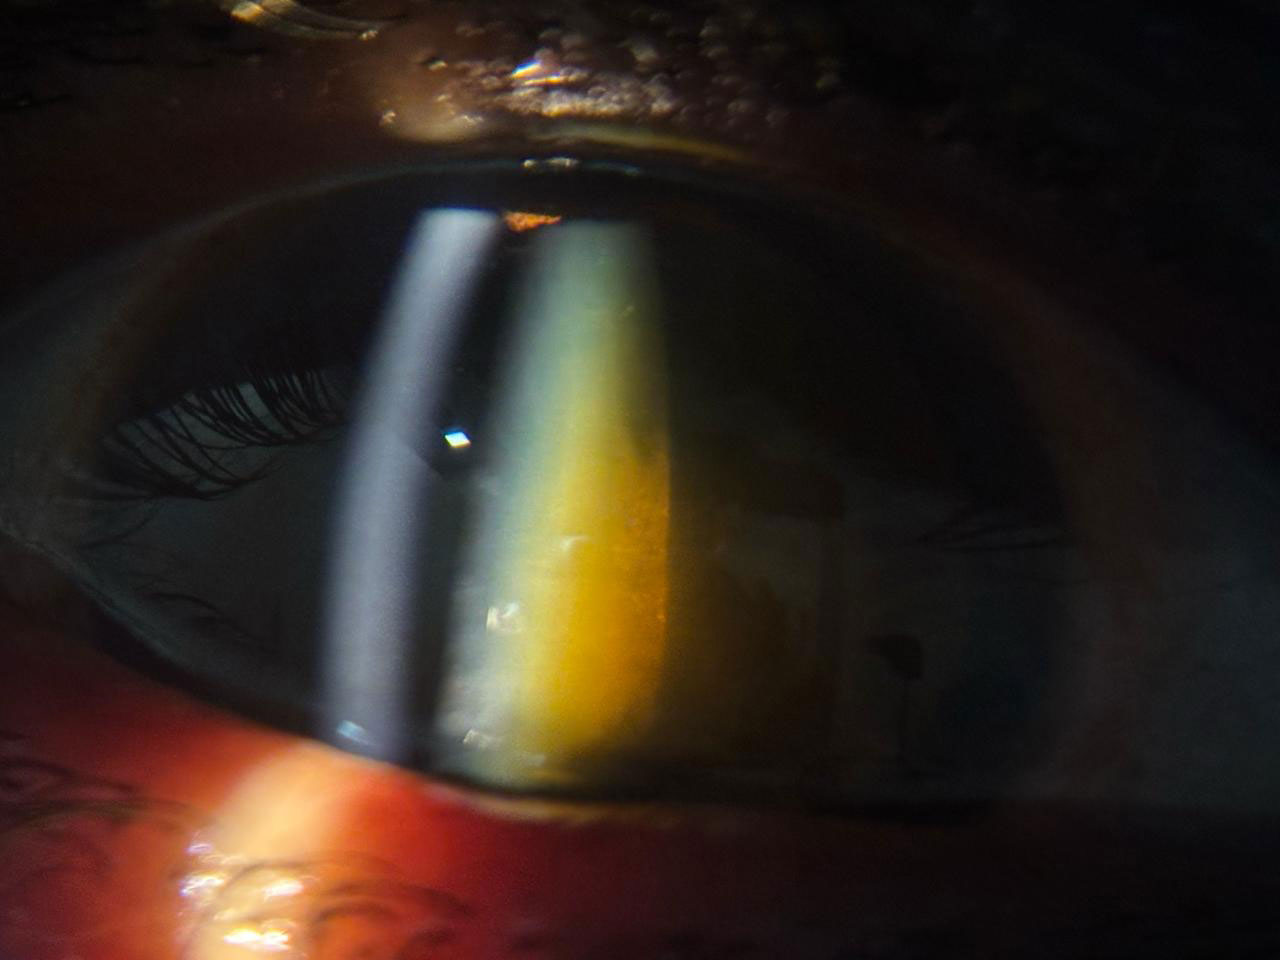

Chalazion – Successful Surgical Management At Vivaan ENT & Eye Clinic, we regularly manage eyelid conditions such as chalazion with safe, effective, and minimally invasive procedures. Recently, a patient underwent chalazion incision and curettage, performed by Dr. Veena Karkhele (Garje) under local anesthesia. The procedure was completed smoothly, and the patient had an excellent post-operative recovery with significant relief from swelling and discomfort.